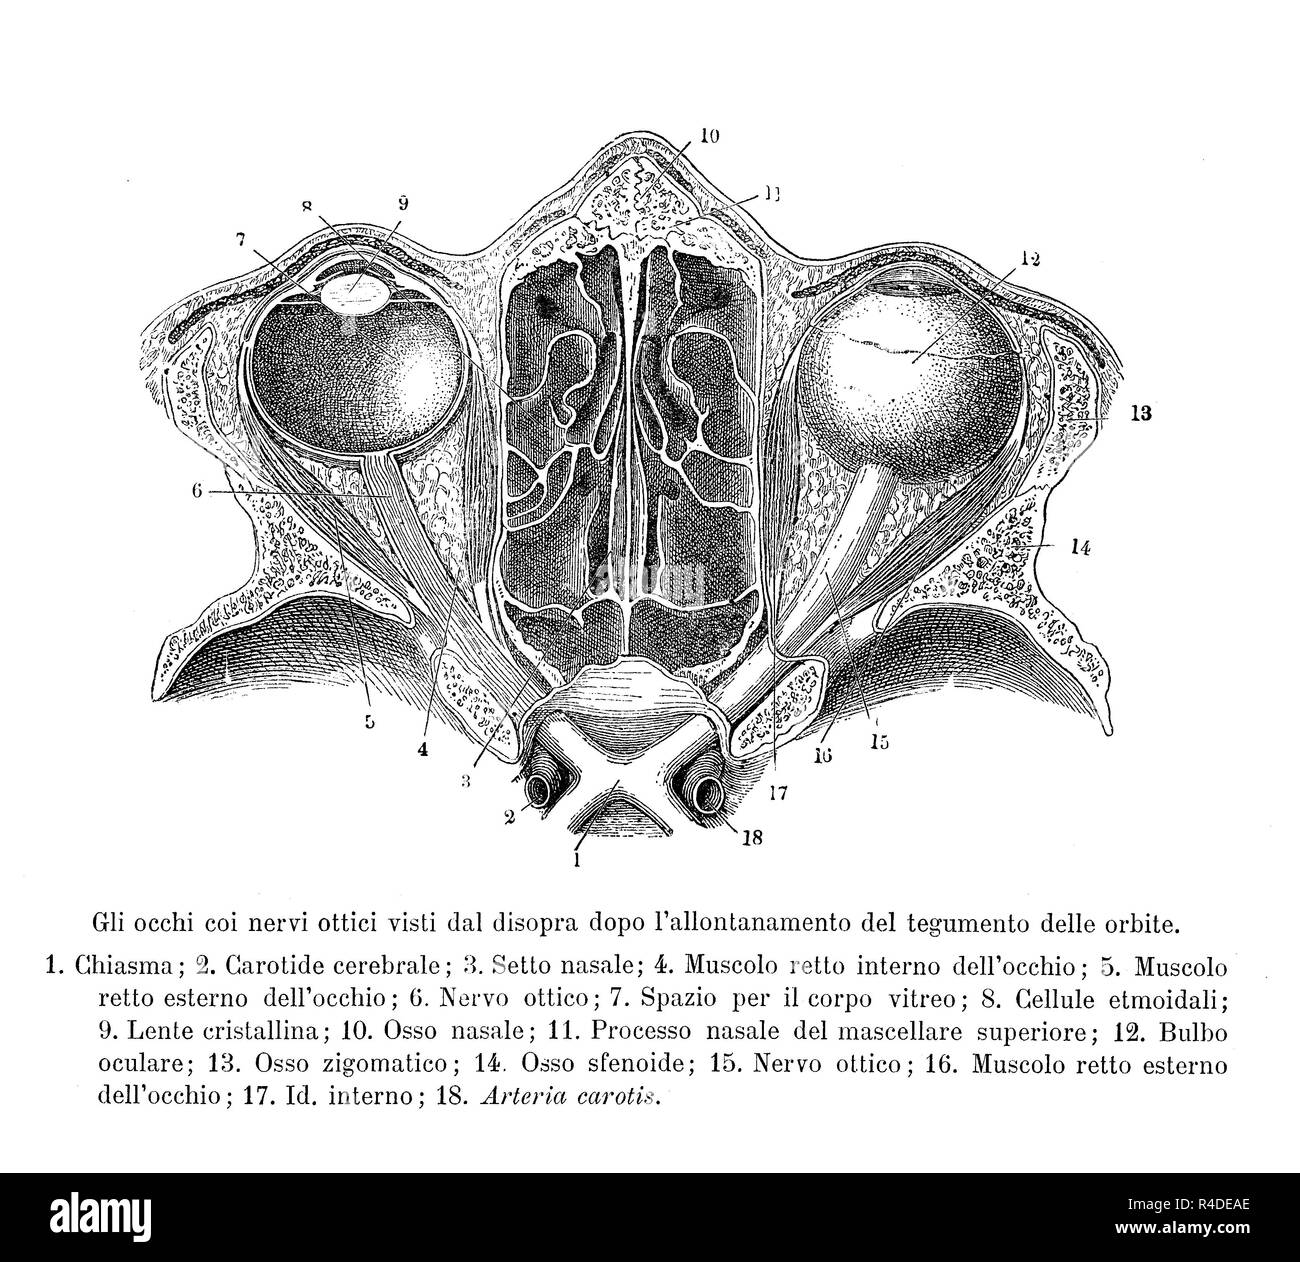

Vintage illustration de l'anatomie, la section transversale des droits de l'optique supérieure de nerfs, avec des descriptions anatomiques en italien Banque D'Imageshttps://www.alamyimages.fr/image-license-details/?v=1https://www.alamyimages.fr/vintage-illustration-de-l-anatomie-la-section-transversale-des-droits-de-l-optique-superieure-de-nerfs-avec-des-descriptions-anatomiques-en-italien-image226490054.html

Vintage illustration de l'anatomie, la section transversale des droits de l'optique supérieure de nerfs, avec des descriptions anatomiques en italien Banque D'Imageshttps://www.alamyimages.fr/image-license-details/?v=1https://www.alamyimages.fr/vintage-illustration-de-l-anatomie-la-section-transversale-des-droits-de-l-optique-superieure-de-nerfs-avec-des-descriptions-anatomiques-en-italien-image226490054.htmlRFR4DEAE–Vintage illustration de l'anatomie, la section transversale des droits de l'optique supérieure de nerfs, avec des descriptions anatomiques en italien